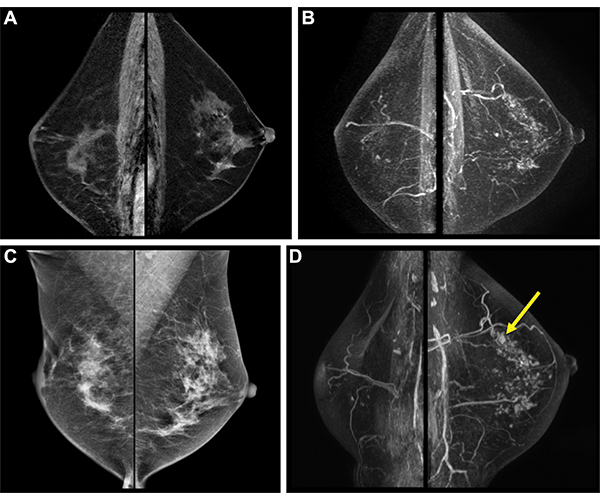

Postoperative surveillance images in a 54-year-old woman who had undergone right breast–conserving surgery and postoperative radiation therapy 2 years prior for stage III hormone receptor–positive invasive ductal carcinoma. She had completed adjuvant chemotherapy and was on endocrine therapy. She had no family history of breast cancer and had not been tested for the BRCA1/2 genes. (A) Bilateral sagittal contrast-enhanced T1-weighted and (B) maximum intensity projection images from baseline surveillance breast MRI show asymmetric moderate background parenchymal enhancement in the left breast. (C) Surveillance mammograms acquired within 6 months of surveillance breast MRI show heterogeneously dense breasts. (D) Subsequent surveillance breast MRI scans acquired 2 years after baseline surveillance breast MRI show a small irregular enhancing mass in the left upper breast (arrow). Biopsy and surgical pathologic examination revealed a 0.8-cm ductal carcinoma in situ.

https://doi.org/10.1148/radiol.220440 © RSNA 2022